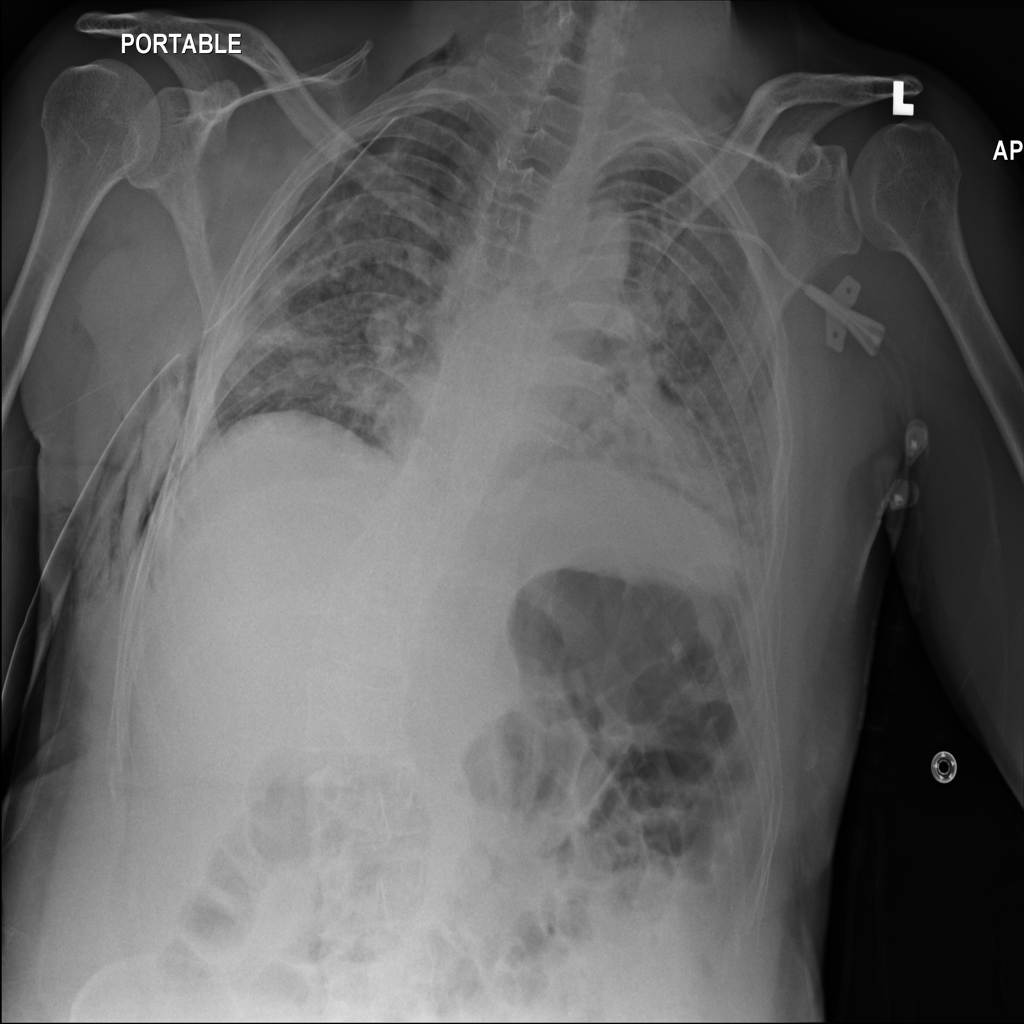

Showing up to 90 reference images for Pneumothorax.

PAT-4639 · IMG-011Pneumothorax

PAT-4639 · IMG-011

AP